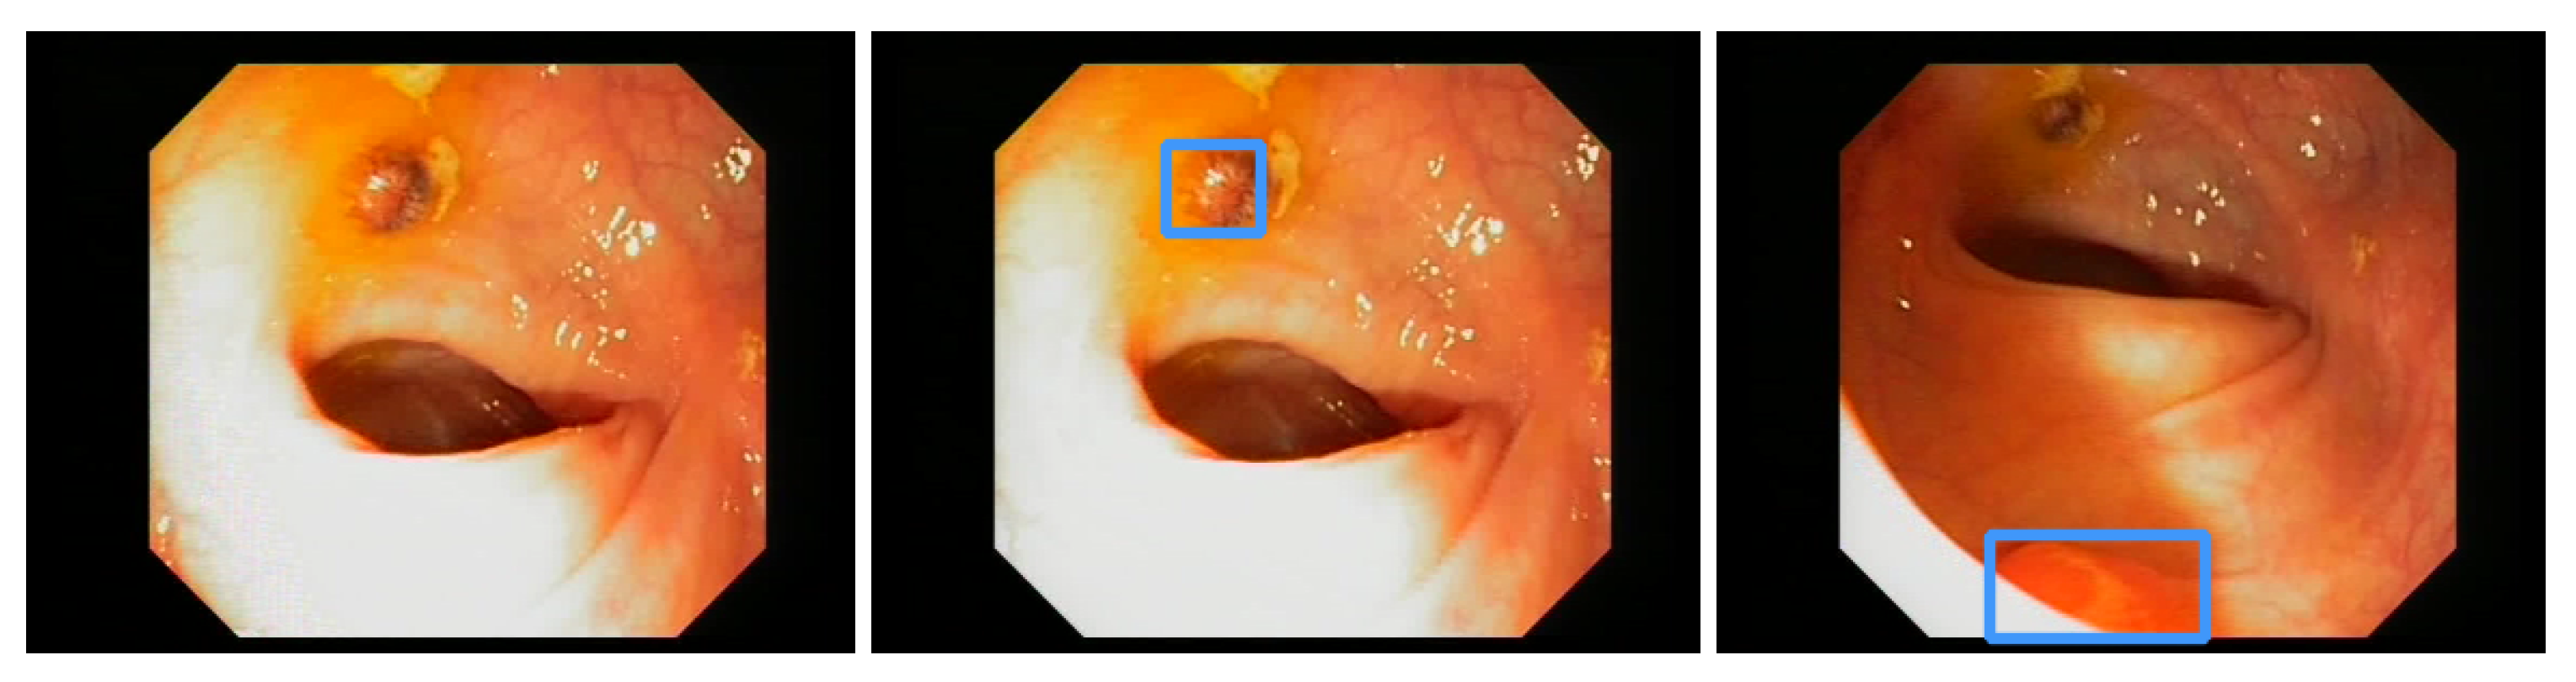

Additionally, the polyp-detection system was publicly funded and developed by computer engineers and endoscopists in the same workgroup to ensure high-quality polyp detection. Figure 1 shows the results of the polyp-detection system. To overview existing work and properly allocate our paper in the literature, we describe a brief history from general polyp detection with handcrafted features to state-of-the-art polyp detection with deep learning techniques.

3.2. EndoData Evaluation

Our own validation set (EndoData) allows us to detect polyps more precisely and accurately. Table 8 shows an overview of the videos in the dataset and Figure 13 shows examples of the dataset. The EndoData dataset records sequences as the polyp appears in the scene. Therefore, polyps are marked precisely with their first appearance. In comparison, the polyp sequence of the CVC-VideoClinicDB dataset might not start when the polyp is already detected. Those early seconds are crucial as the gastroenterologist has to identify and not miss the polyp during this time. If the polyp is not detected in the early sequence, it increases the risk of missing it. As we like to focus on this early detection, we introduce a second metric that can just be evaluated with a dataset like ours. This metric marks the seconds from first seeing the polyp to first detecting the polyp. We call it first detection time (FDT). Additionally, we compute the FPs and the false positive rate (FPR) per video (Table 10 and Table 11).